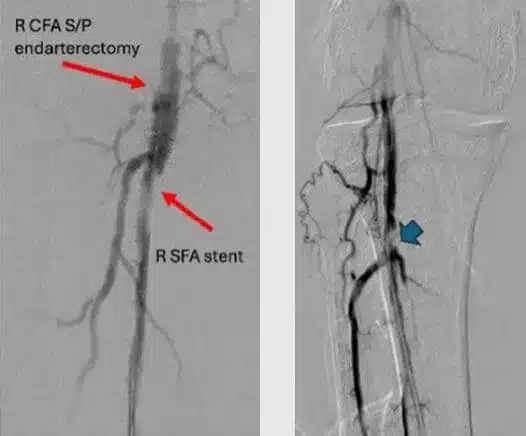

An 83-year-old male with past medical history of diabetes, hypertension, coronary artery disease, a prior bypass, and peripheral artery disease, including right lower extremity chronic limb threatening ischemia (CLTI) with a non-healing right foot ulcer with osteomyelitis lasting greater than 12 months (Figure 1), and a previously treated common femoral artery (CFA) with endarterectomy, returned for right superficial femoral artery (SFA) and tibial chronic total occlusion (CTO) intervention.